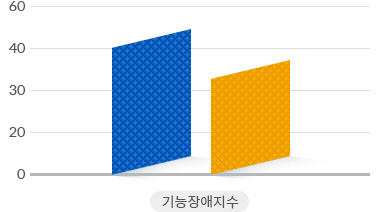

척추관협착증 수술 VS 비수술 치료 기능장애 변화 비교

수술치료

수술치료

비수술치료

비수술치료